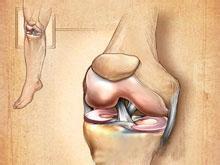

肺栓塞和下肢静脉血栓

疾病介绍:肺栓塞、肺动脉高压肺栓塞(pulmonary embolism, PE)是以各种栓子阻塞肺动脉系统为其发病原因的一组疾病或临床综合征的总称,以下肢静脉血栓脱落引起…【详细】

肺栓塞和下肢静脉血栓

疾病介绍:肺栓塞、肺动脉高压肺栓塞(pulmonary embolism, PE)是以各种栓子阻塞肺动脉系统为其发病原因的一组疾病或临床综合征的总称,以下肢静脉血栓脱落引起…【详细】

肺栓塞和下肢静脉血栓

疾病介绍:肺栓塞、肺动脉高压肺栓塞(pulmonary embolism, PE)是以各种栓子阻塞肺动脉系统为其发病原因的一组疾病或临床综合征的总称,以下肢静脉血栓脱落引起…【详细】

肺栓塞和下肢静脉血栓

疾病介绍:肺栓塞、肺动脉高压肺栓塞(pulmonary embolism, PE)是以各种栓子阻塞肺动脉系统为其发病原因的一组疾病或临床综合征的总称,以下肢静脉血栓脱落引起…【详细】

肺栓塞和下肢静脉血栓

疾病介绍:肺栓塞、肺动脉高压肺栓塞(pulmonary embolism, PE)是以各种栓子阻塞肺动脉系统为其发病原因的一组疾病或临床综合征的总称,以下肢静脉血栓脱落引起…【详细】

肺栓塞和下肢静脉血栓

疾病介绍:肺栓塞、肺动脉高压肺栓塞(pulmonary embolism, PE)是以各种栓子阻塞肺动脉系统为其发病原因的一组疾病或临床综合征的总称,以下肢静脉血栓脱落引起…【详细】

肺栓塞和下肢静脉血栓

疾病介绍:肺栓塞、肺动脉高压肺栓塞(pulmonary embolism, PE)是以各种栓子阻塞肺动脉系统为其发病原因的一组疾病或临床综合征的总称,以下肢静脉血栓脱落引起…【详细】